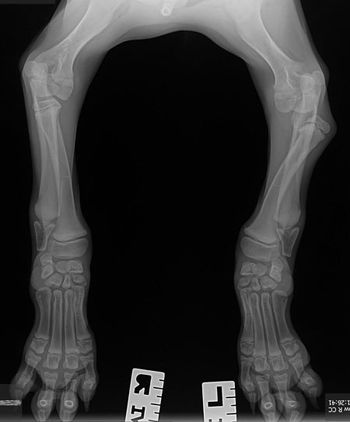

Are you an X-ray expert? Test your skills with this case of an unsteady standard poodle pup.